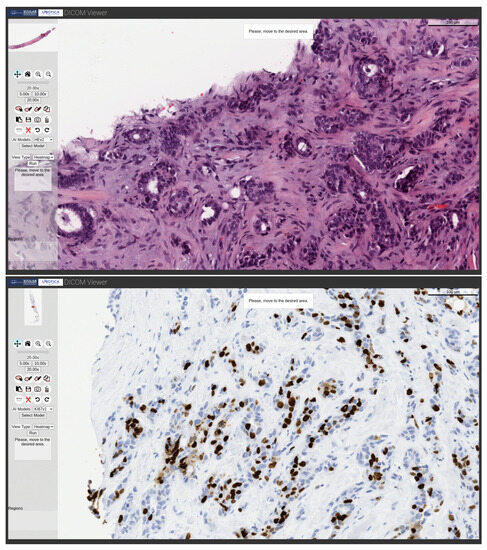

Figure 3 shows the visualization of various WSI samples from various biopsies stained with H&E, Ki67 and HER2, as well as the selection of regions of interest (ROI) on the WSIs using the editing tools of the viewer.

Figure 3. Visualization of different WSIs samples stained with H&E, Ki-67 and HER2, as well as ROI selection.